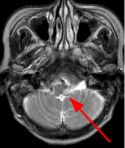

MRI Findings: In the supratentorial regions, some atrophy and chronic small vessel deep white matter ischemic changes were observed (Fig. 1) but no acute lesion or infarct was observed on MR diffusion. In the posterior fossa, however, a subtle small 1 cm hyperintensity can be seen in the left side of medulla on T2 weighted (Fig. 2) and FLAIR images (Fig. 3). This can be seen with an infarct, but its age would remain indeterminate. The MR diffusion image (Fig. 4) shows hyperintensity in the same region consistent with an acute infarct (arrows) as opposed to chronic ischemic changes.

Final Diagnosis: Based on the MR appearance, diagnosis of acute lateral medullary infarct was provided. This is a classic appearance of a posterior inferior cerebellar artery (PICA) infarct (PICA Syndrome), which may have thrombosed.